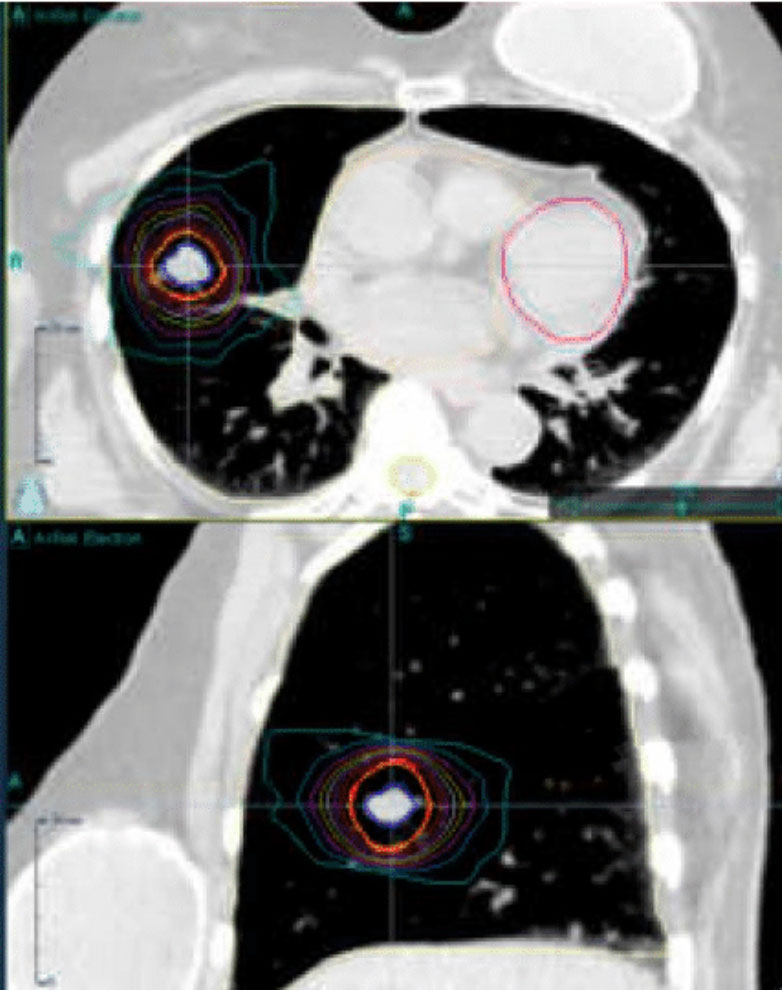

Capital Radiosurgery Centers (CRC) provides highly precise, non-invasive lung cancer treatment using advanced radiation technologies such as stereotactic radiosurgery (SRS), stereotactic body radiation therapy (SBRT), and intensity-modulated radiation therapy (IMRT). All treatments are carefully planned based on clinical appropriateness and delivered by board-certified radiation oncologists, medical physicists, dosimetrists, nurse navigators, and other specialized oncology professionals.

These treatments target lung tumors with exceptional accuracy—even accounting for tumor movement caused by breathing—helping protect surrounding healthy tissue and preserve lung function and quality of life. Care is delivered in an independent, outpatient setting, bringing hospital-level technology into the community without the need for surgery or overnight hospital stays.

SBRT is an advanced radiation therapy that targets tumors with sub-millimeter accuracy. Unlike conventional radiation, which may take weeks, SBRT completes treatment in days—protecting healthy tissue and helping patients maintain their daily routines.

Technology Designed for Precision

We use CyberKnife® and Varian TrueBeam® to treat tumors anywhere in the body, even those that move with breathing or normal motion. Advanced imaging and real-time tracking mean no restrictive frames, no breath-holding, and no invasive procedures.